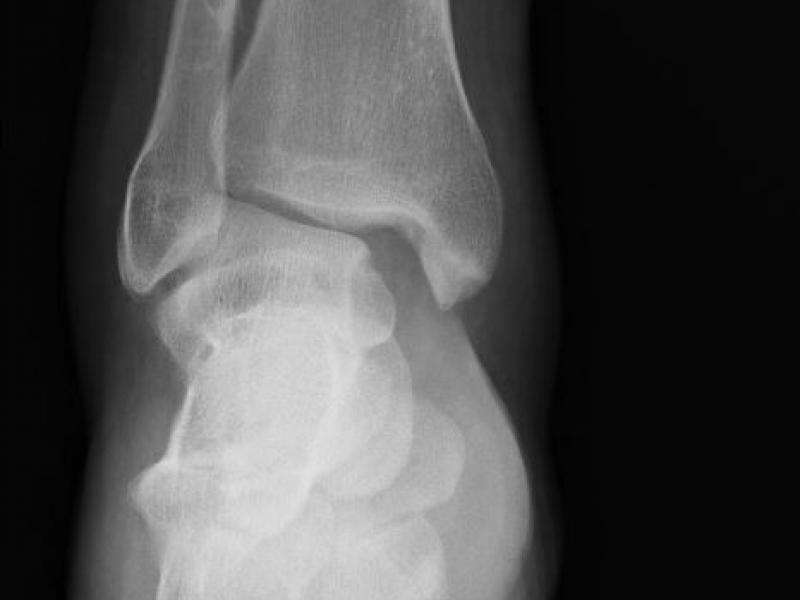

Critical Cases - Ankle dislocation!!

February 16 2021

History 29 yo male with no medical problems presents after